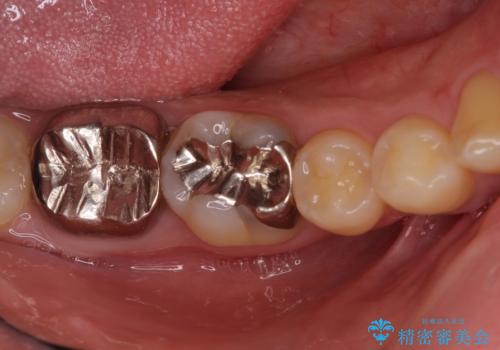

銀歯を白くしたい セラミックによる審美歯科治療

- 治療中の前歯と口腔内にある銀歯が気になるとのことで来院された患者様です。

土台に含まれている金属も含め、口腔内の金属は全て除去し、根管治療が必要な歯は根管治療を行い、オールセラミッククラウンやセラミックインレーにて治療することとしました。